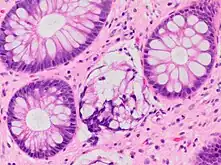

Paneth cell (pictured) or gastric metaplasia (only applies in the left colon and rectum)

Other findings include basal plasmacytosis and mucin depletion.[4] Histopathology findings generally associated with active colitis include:[4]

Neutrophilic cryptitis (neutrophils within crypt epithelium)

Crypt abscesses (luminal neutrophilic aggregates)

Gland destruction

Ulceration (seen here as absence of epithelium, and granulation tissue with many fibroblasts)